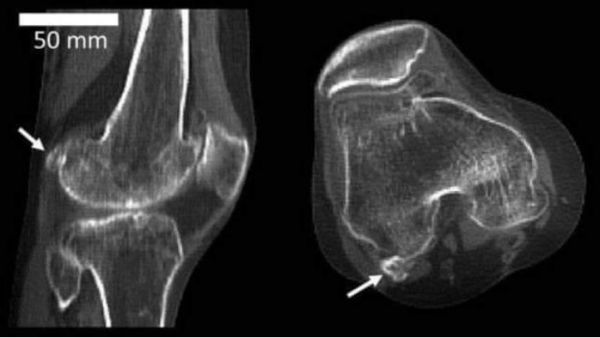

膝关节上一个名叫豆骨(fabella)的小骨头先是慢慢消失,但在过去几百年中,又神奇地出现了,而且越来越多。

膝关节上的豆骨(箭头处)来源:徐德文科学频道